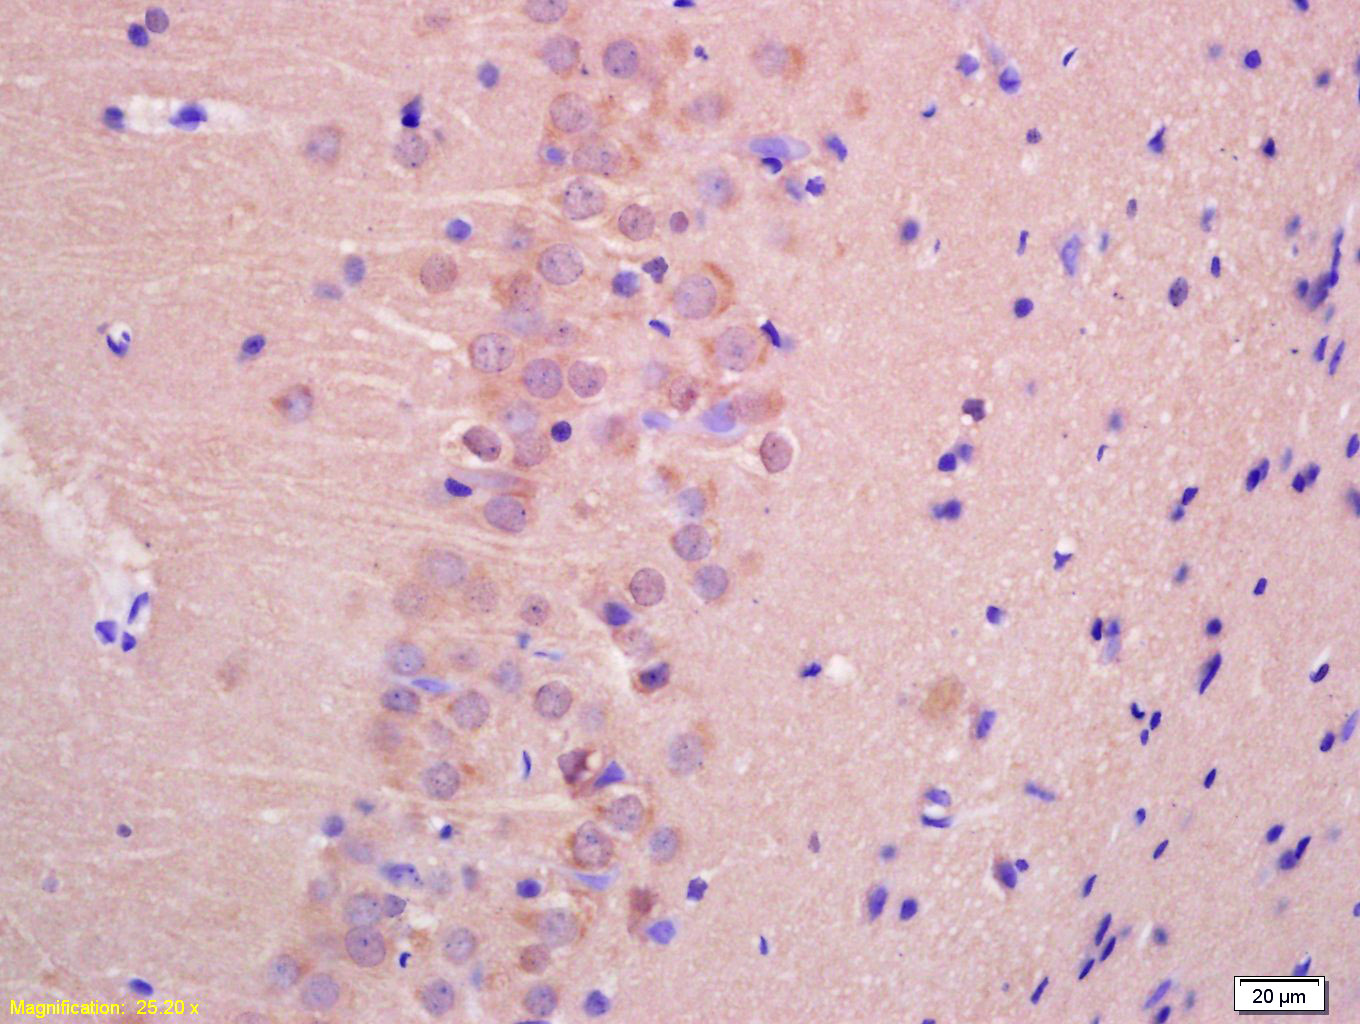

Paraformaldehyde-fixed, paraffin embedded (Rat brain); Antigen retrieval by boiling in sodium citrate buffer (pH6.0) for 15min; Block endogenous peroxidase by 3% hydrogen peroxide for 20 minutes; Blocking buffer (normal goat serum) at 37°C for 30min; Antibody incubation with (TTC33) Polyclonal Antibody, Unconjugated (bs-9146R ) at 1:500 overnight at 4°C, followed by a conjugated secondary (sp-0023) for 20 minutes and DAB staining.

Tissue/cell: rat brain tissue; 4% Paraformaldehyde-fixed and paraffin-embedded; Antigen retrieval: citrate buffer ( 0.01M, pH 6.0 ), Boiling bathing for 15min; Block endogenous peroxidase by 3% Hydrogen peroxide for 30min; Blocking buffer (normal goat serum,C-0005) at 37℃ for 20 min; Incubation: Anti-TTC33 Polyclonal Antibody, Unconjugated(bs-9146R) 1:200, overnight at 4°C, followed by conjugation to the secondary antibody(SP-0023) and DAB(C-0010) staining